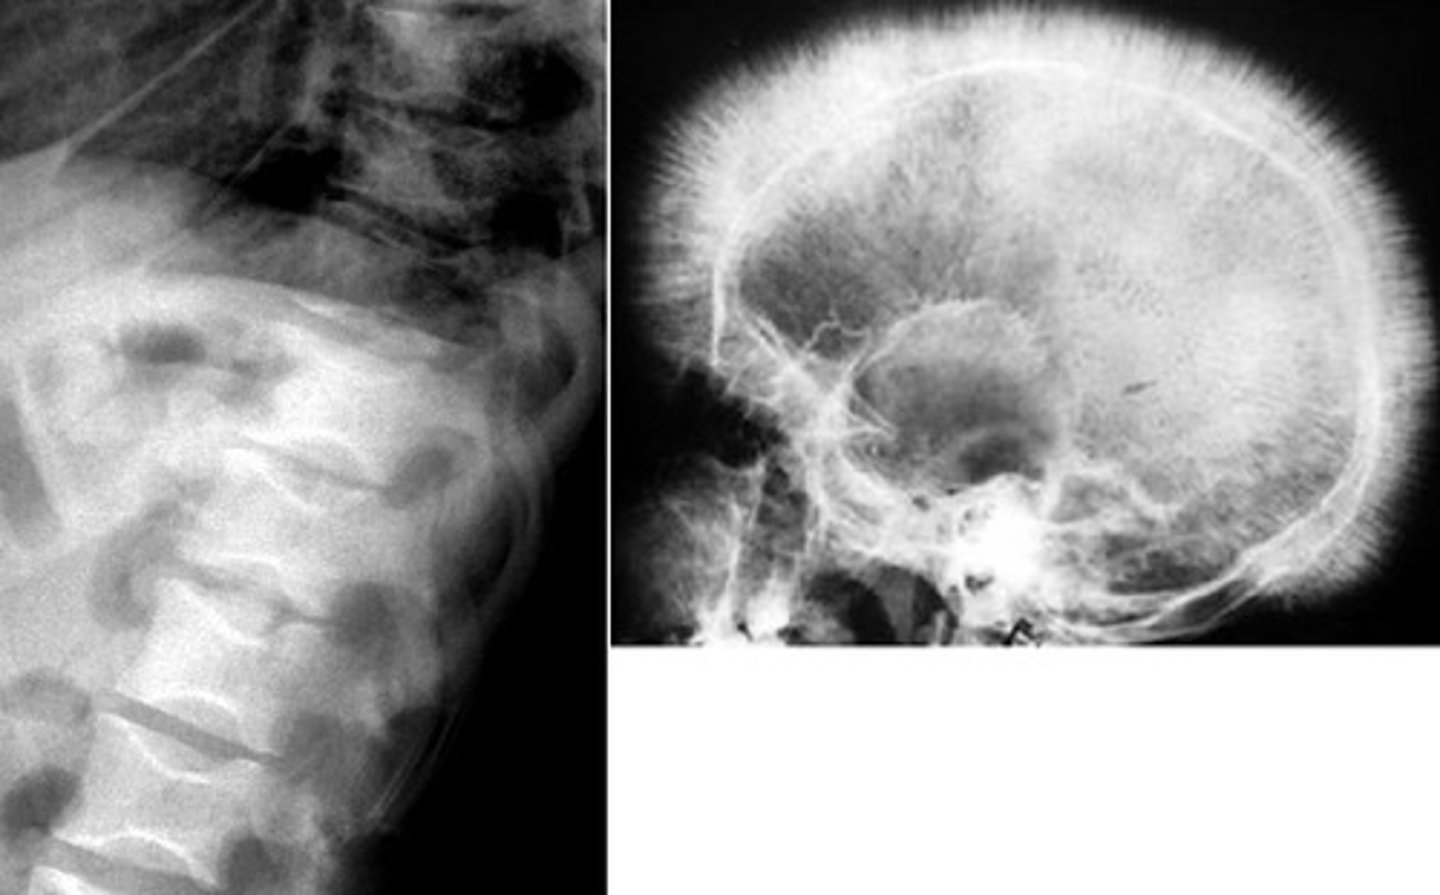

hair on end appearance skull

what are the radiologic findings associated with beta thalassemia major?

accentuated trabeculae due to bone marrow hyperplasia

why does hair on end appearance skull happen in beta thalassemia?